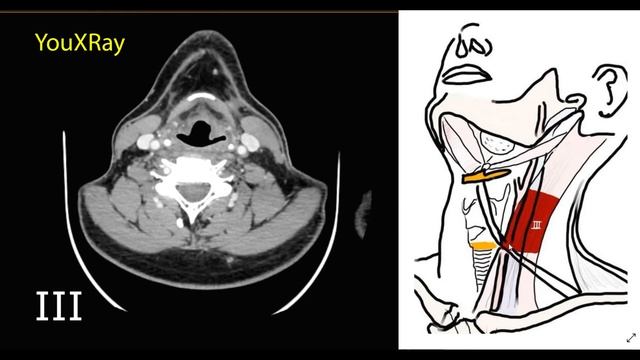

Уровни лимфоузлов шеи на КТ    |Лучевая диагностика|